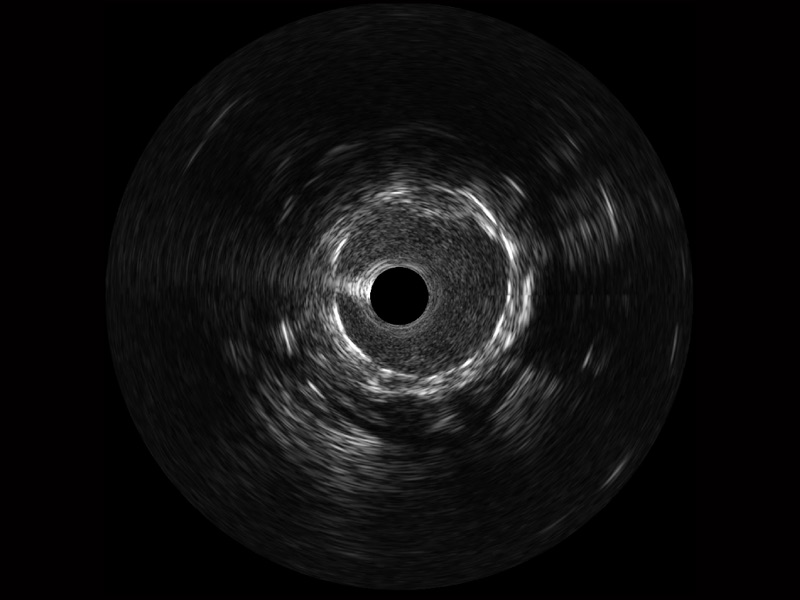

• db真人体育官网宽频IVUS图像

• 传统IVUS图像

对比传统IVUS导管成像,db真人体育官网宽频IVUS图像的近场支架梁显影更细腻,远场中膜外血管仍清晰可辨,兼顾远中近,兼顾分辨力与穿透深度